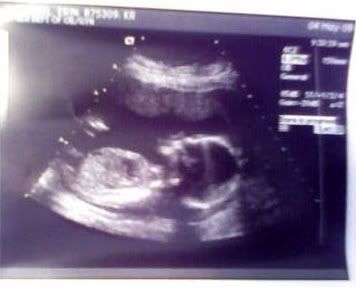

Today I am 19 weeks 2 days, but I had my 20 week ultrasound today. She is still a girl!! She weighed 11oz and is measuring right on target.